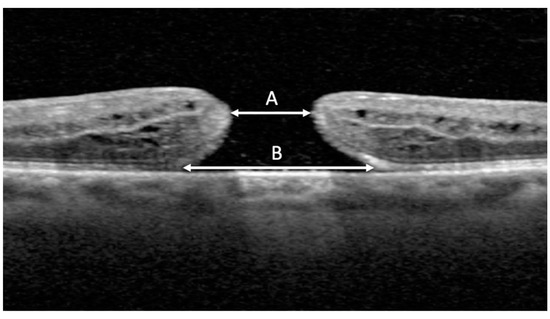

MLD, BD, and closure status following surgery were measured using spectral domain-optical coherence tomography (OCT) imaging (Heidelberg Spectralis, Heidelberg Engineering, Heidelberg, Germany) with a volume-per-cube acquisition protocol (20° × 20°, 49 B-scans, 768 A-scans per line) and 9 times image averaging. MLD was measured in 1:1 μm format using the measure distance overlay tool. MLD was measured between the nearest ends of broken macular tissue in the scan with the widest hole dimensions [12] (Figure 1). Any operculated component of the hole was excluded from the MLD measurement [12]. BD was measured at the level of the retinal pigment epithelium layer between the broken macular tissue in the same scan that the MLD measurements were taken [12]. MLD and BD measurements were conducted by an independent investigator (MNP), and consensus with a second grader (CCW) was performed for cases that were perceived as unclear by the initial investigator. MLD was categorized into three size ranges: <250 μm (small), 250–400 μm (medium), and >400 μm (large) [13] based on traditional macular hole staging [1,12]. BD was also categorized into three size ranges: <577.0 μm (small), 577.0–890.3 μm (medium), and >890.3 μm (large). These groups were created by dividing the range of BD measurements from the study group equally into thirds.

Figure 1. OCT image measurement with distance overlay tool. Minimum linear diameter (MLD) (A) was measured between nearest ends of broken macular tissue in the scan with the widest hole dimensions. Basal diameter (BD) (B) was measured at the level of the retinal pigment epithelium.